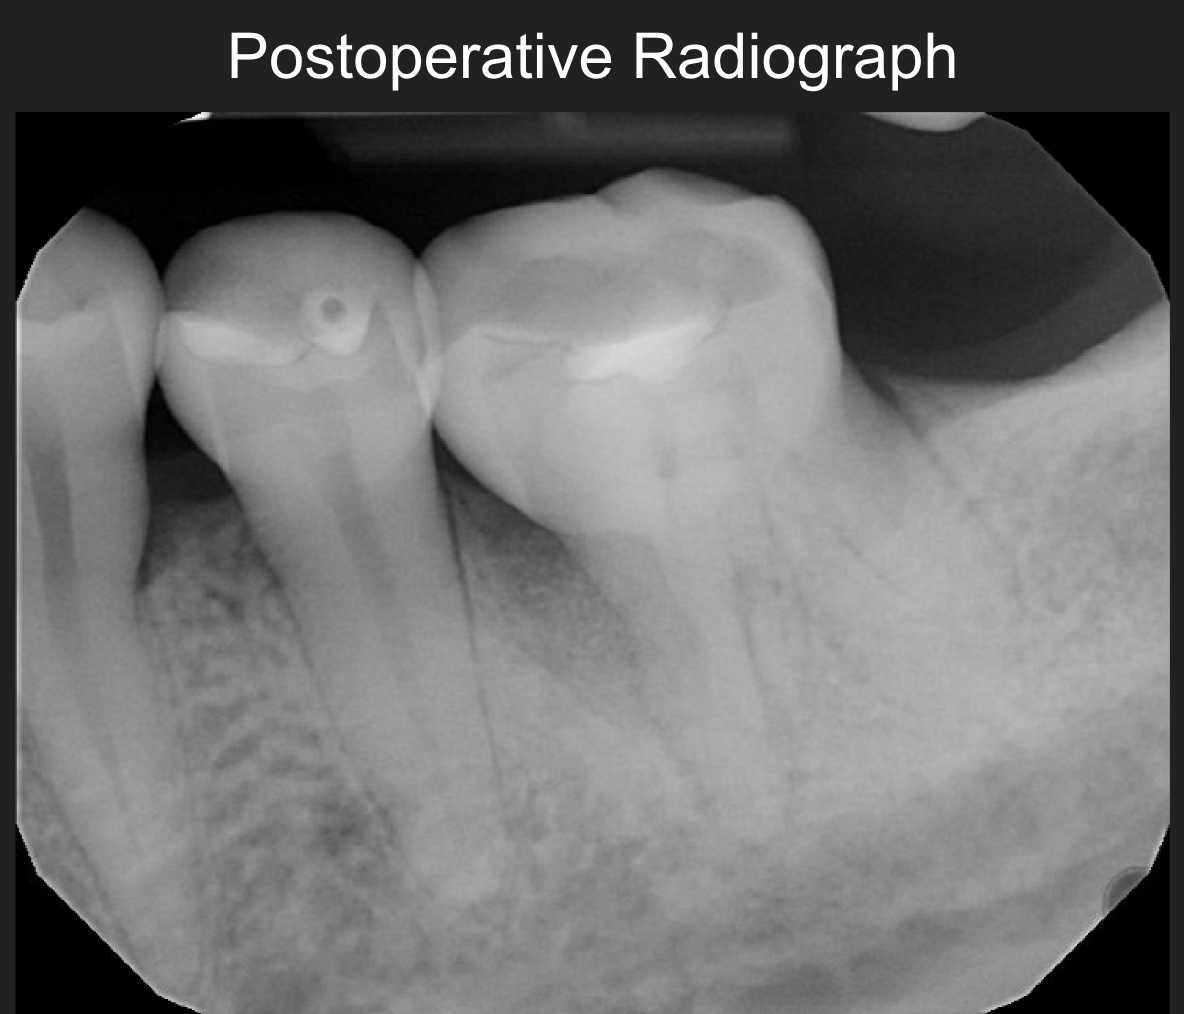

The patient remained compliant with a three-month periodontal maintenance schedule. At one year post-operatively,

radiographic bone fill was maintained, with #19-m presenting 4 mm probing depths, no bleeding on probing,

and no mobility. All treatment goals were successfully achieved.